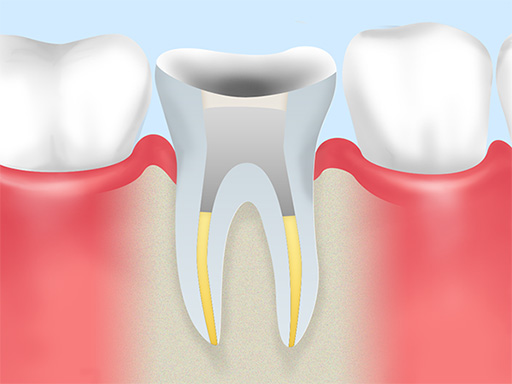

根管充填 -

根管内を清掃・乾燥させた後、隙間なくお薬(充填材)を詰めて封鎖します。

土台作り -

歯の補強と再感染防止のため、被せ物の土台を作ります。